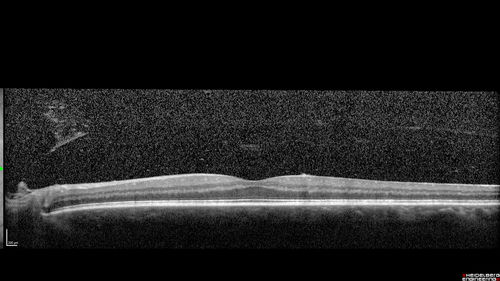

PDR and Vitreous Hemorrhage - High Risk Left Eye - Low Risk Right Eye

50 year old man with type I diabetes mellitus for 26 years. New Vitreous Hemorrhage in the left eye. Both eyes have NVE. Both also have foveal hypoplasia

Vitreous Hemorrhage and Proliferative Diabetic Retinopathy - Low risk right eye - High Risk Left Eye - Also Fovea Plana